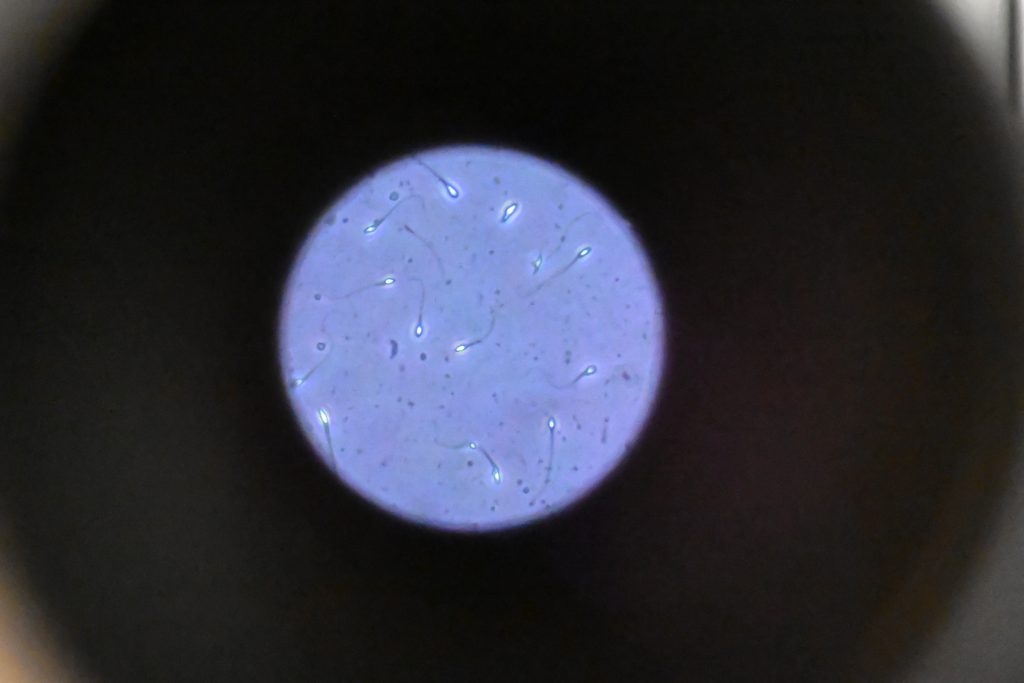

السائل المنوي عبارة مزيج من السوائل التي تفرزها البروستاتا والحويصلات المنوية والخصيتان. ومن ثم “من الطبيعي أن يظهر السائل المنوي تقلبات طفيفة في اللون أو الملمس أو الرائحة” وفق تقرير لشبكة “سي إن إن”.

وقد تختلف “جودة” السائل المنوي من يوم لآخر أو بين القذف والآخر، لكن بشكل عام، يجب أن يحتوي على تركيز من الحيوانات المنوية لا يقل عن 15 مليون حيوان منوي لكل ملليلتر، مع وجود 40 في المئة على الأقل تظهر حركة و4 في المئة تظهر شكلًا طبيعيًا، وفقاً لمنظمة الصحة العالمية.

وعلى النقيض من ذلك، قد يشير السائل المنوي المائي إلى انخفاض عدد الحيوانات المنوية أو تكرار القذف، مما قد يؤثر مؤقتاً على جودة الحيوانات المنوية.

وقد يعاني الرجال الذين يقذفون عدة مرات يوميا من انخفاض مؤقت في عدد الحيوانات المنوية وحركتها، والذي عادةً ما يعود إلى طبيعته مع انخفاض التكرار.